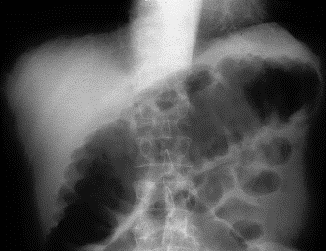

Toxisk megacolon** (bilden (buköversikt)) (Inflammationen i slemhinnan påverkar serosan i kolon som ger paralys av muskellager och tarmen blåser upp sig och följden kan bli avföring i bukhåla med peritonit)